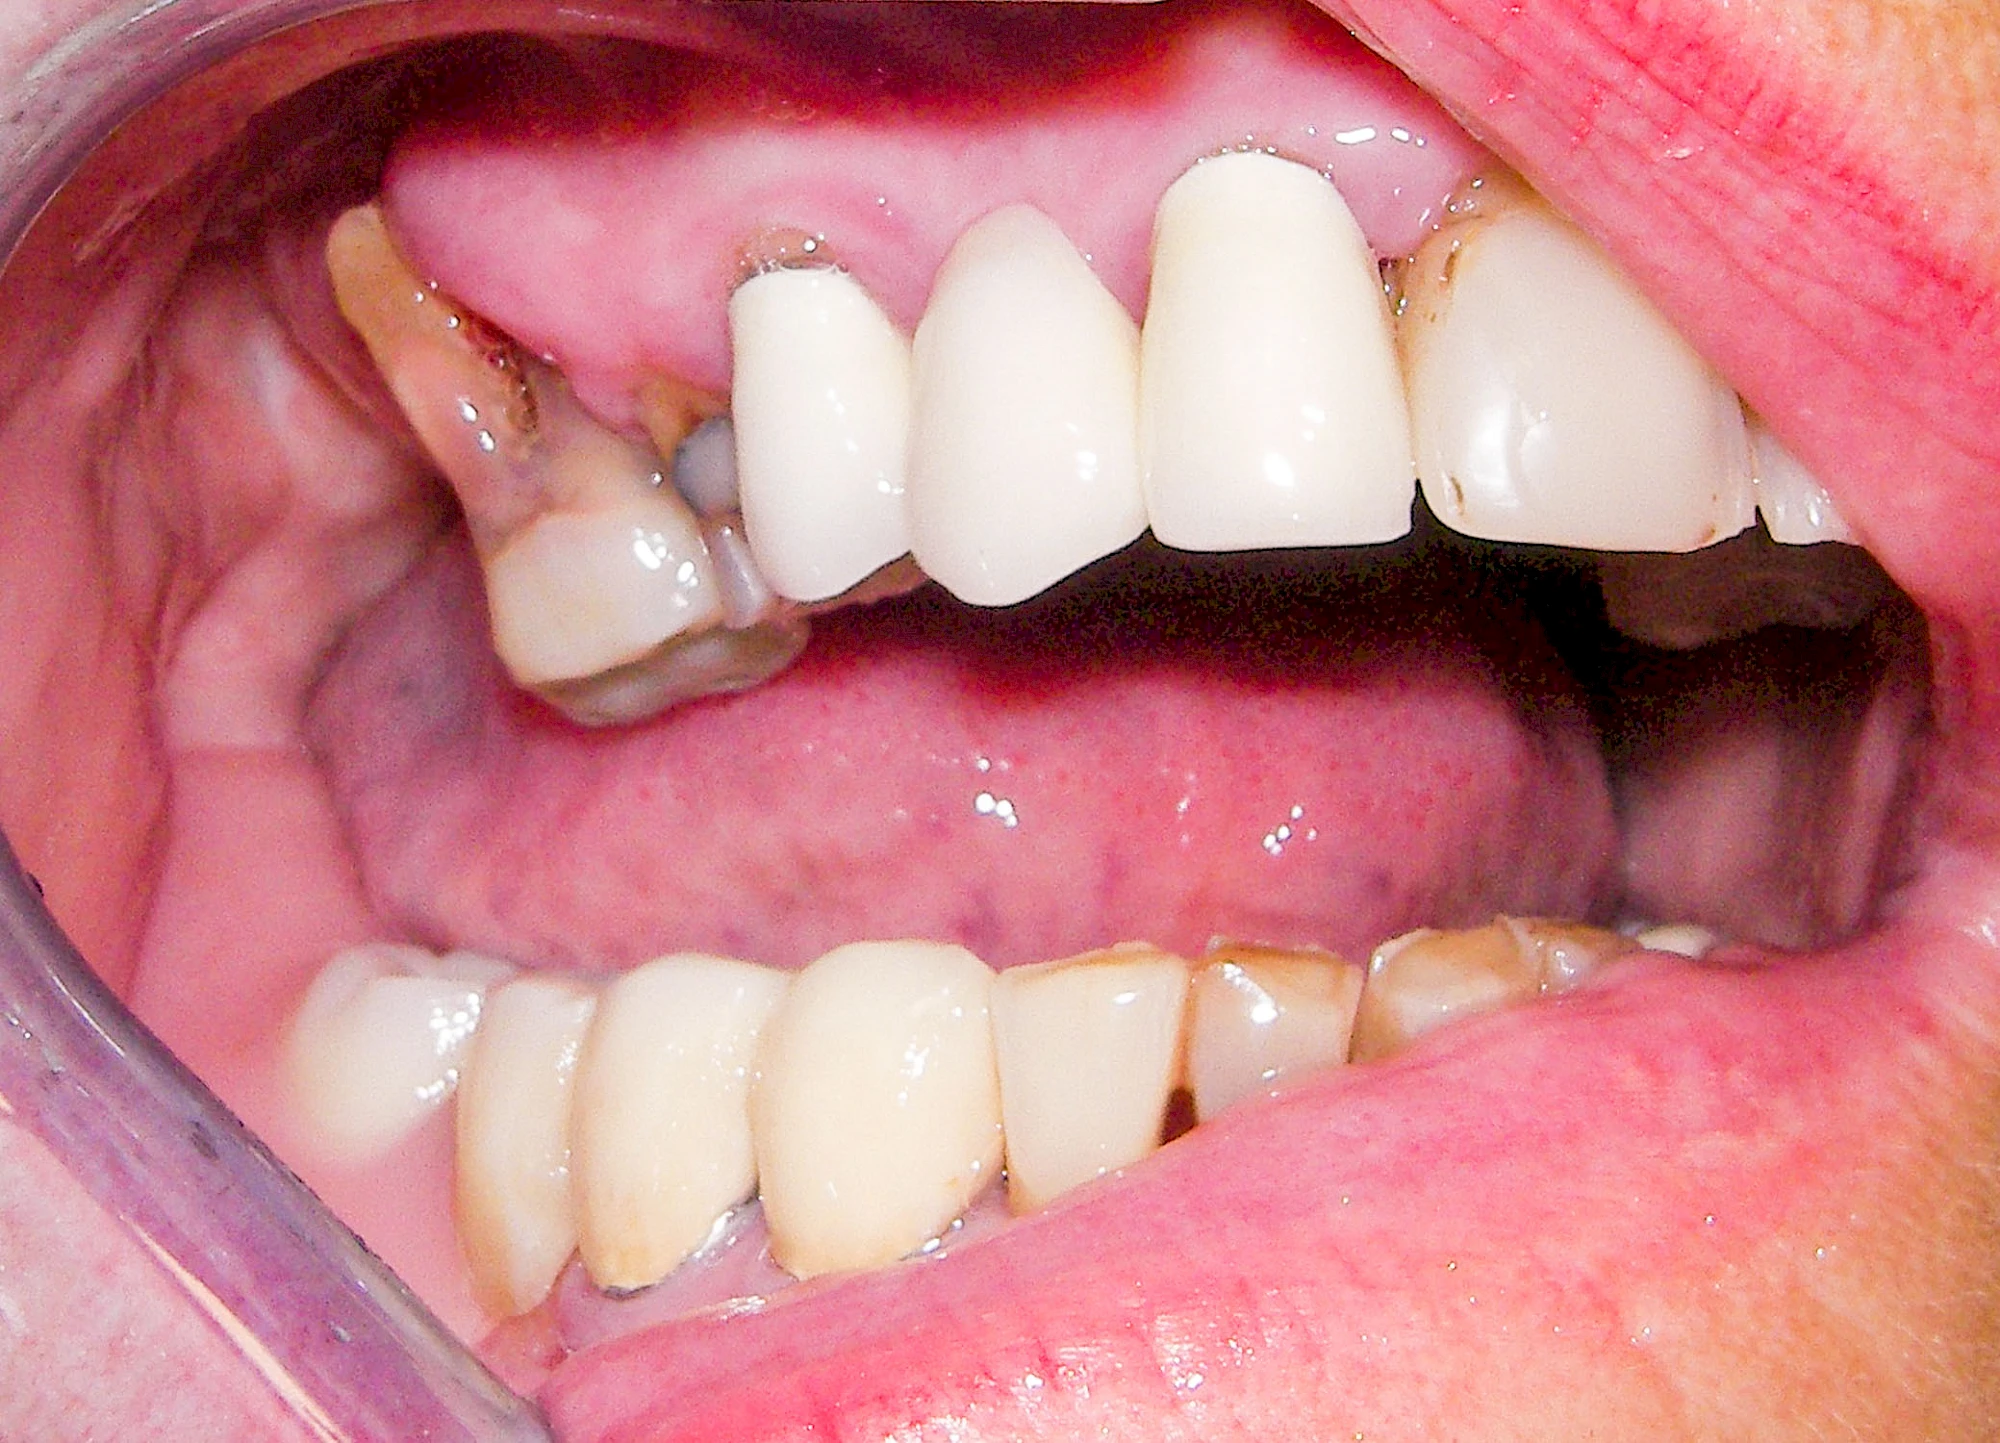

Ist zunächst nur das Zahnfleisch von der Entzündung betroffen, spricht man von Gingivitis. Später, wenn auch der Knochen um die Zähne herum entzündet ist, spricht man von einer Parodontitis. Bei der Parodontitis wird der Knochen nach und nach abgebaut und das Zahnfleisch zieht sich zurück. Die Zahnhälse und Zahnwurzeloberflächen liegen mehr und mehr frei. Die Zähne werden zunehmend lockerer und fallen schließlich aus.